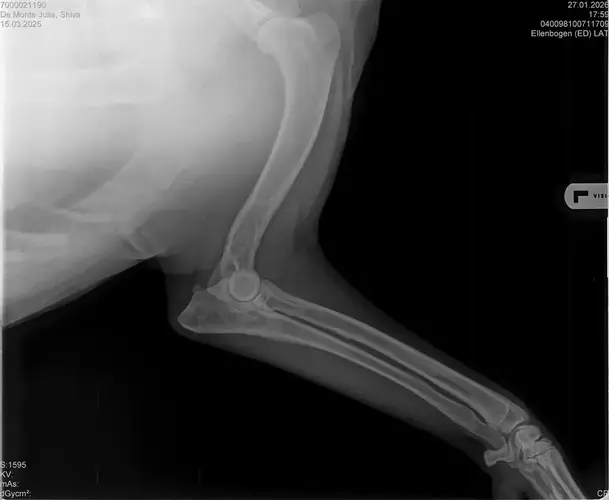

Vorige Woche kam mir Shiva verändert vor, nicht der aufgeweckte Spaßvogel der er sonst ist. Ich dacht vl ist er im Garten iwie blöd ausgerutscht weil unser gesamtes Grundstück über Wochen von einer dicken Eisschicht überzogen war. Er lag viel rum, zuviel da er doch zu den Wirbelwinden unter den Junghunden gehört. Er quetschte sich zum schlafen an mich ran, was auch untypisch für ihn ist. Er ist immer so „iiiii fass mich nicht an“. Ich nehms ihn nicht böse er ist nicht der große Kuschler :D Hat er wohl von mir :D :D aber er pickte nur an mir dran, ruhen ohne Körperkontakt war nicht möglich. Fand ich schön aber da ich wusste dass es nicht Shiva ist machte ich mir schon Sorgen… Am nächsten Tag wollte ich ihn bürsten alles war wie immer, er legte sich hin und sah mir zu wie ich einen Fellberg stapelte. Bei seinen Hinterpfoten hörte ich auf und dachte mir ich fühl mal vorsichtig.. Plötzlich knurrte er mich an vor Schreck weil ich damit überhaupt nicht gerechnet hatte zuckte ich reflexartig zurück (was lt Trainerin ein Fehler war)… Aber ich hab nicht mit einer derartigen Reaktion gerechnet, Shiva hatte schon 2 kleine Verletzungen die ich ohne Probleme verarzten konnte. Am nächsten Tag gings ab zum TA. Mit Maulkorb da ich nichts riskieren wollte. Nach der Untersuchung wo er auch mehrmals knurrte gings ab zum röntgen. Und das riss mir den Boden unter den Füßen weg. Dann die Aussage von der TA „ich weiß sie wollen einen gesunden jungen Hund aber das ist Shiva leider nicht“. Was jetzt? Er ist so ein aufgewecktes Kerlchen, absolute Lieblingsbeschäftigung ist Parcour. Er macht es so gern, ja auch UO und Suchspiele aber das leuchten in seinen Augen wenn wir Geräte machen :( (er macht noch keine schweren Geräte wie A Tafeln oder springen… Aber die seichten macht er mit absoluter Leidenschaft.. Ruhe halten über mehrere Monate… nur langsames gehen oder schnüffeln.. puh ich weiß nicht wie ich ihm verbieten soll zu rennen und zu toben… Vl habt ihr Tipps für mich. Im Anhang der Befund und ein paar Bilder vom kleinen Wirbelwind. <3

Ich lese da draus, dass der Hund in mindestens einem Ellenbogen nicht sauber ist, HD "noch zugelassen" oder "mittel" hat, nen' 1er LÜW UND vielleicht sogar OCD. Das wär ja wahnsinnig...

• Naja die Diagnose kommt von einem „Facharzt“, lt TA war ihrerseits alles i.O. Sie wollte noch sicher gehen und die Bilder zur weiteren Befundung einschicken und das kam dabei raus. Und der Therapievorschlag beläuft sich auf Ruhe, Ruhe und noch mehr Ruhe. Und einer Schmertherapie von Gabapentin 800mg 1/2 Tablette 2x tgl, Carprodyl 120mg 1 1/2 Tabletten 1x tgl und TamaCan CBD Tropfen 10-15 Tropfen 2x tgl. 1x in der Woche soll ich telefonisch Auskunft geben wie es Shiva geht. Das ganze mal für 14 Tage. Sie meinte noch sie hat viele Junghunde die ein Leben lang Schmerzmittel nehmem müssten. Die Röhrenknochenentzündung heilt in der Regel von selber der Rest gehört beobachtet… Ich weiß im Moment auch nocht so recht.. Er tut mir nur wahnsinnig leid mit sovielen Diagnosen und für mich war erstmal vorrangig ihn schmerzfrei zu bekommen. Das ist er inzwischen und versteht die Welt nicht mehr warum er nicht wie sonst spielen und arbeiten darf. Im Anhang noch Röntgenbilder falls sich jemand damit auskennt bzw Interesse hat..

• Ok, die Röntgenbilder sind aber auch extrem schlecht.

Panostitis ist idR sehr schmerzhaft, aber nicht unüblich und heilt in der Regel von alleine aus, wichtig dabei ist schonen und Entzündungshemmer zu geben, damit das nicht chronisch wird. Ich denke, dass die Akut bemerkbaren Schmerzen hauptsächlich davon kommen. Also da passt die Empfehlung deiner TÄ für's Erste auf jeden Fall.

Wenn dieser Panostitis-schub rum ist, würde ich dem Rest nochmal nachgehen. Man kann bei Dr. Tellhelm ( SV Gutachter) ein privatgutachten in Auftrag geben, das kostet um die 100€. Da kriegst du halt ne konkrete Einstufung und nicht "verdacht auf" und "könnte hiermit ODER damit in Verbindung stehen", etc.

Ich denke aber, dass du für ein Gutachten von Tellhelm nochmal neu röntgen lassen musst, ich finde, dass das Bild der Hüfte (HD und LÜW wird da beurteilt) und die Draufsicht auf die Ellenbogen (nötig zur Beurteilung von ED) unterirdisch sind!